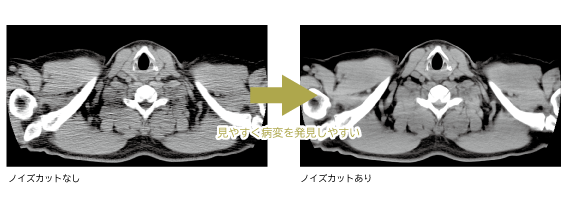

①AI技術(AiCE)を利用したノイズカットによる画質の向上により、病変を発見しやすくなる